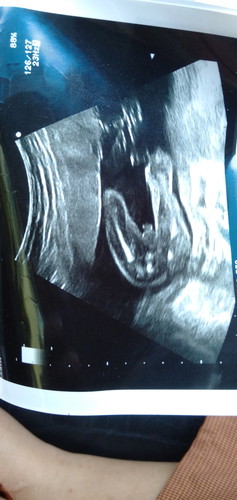

ความรัก

ทีมพฤษภาคมลูกชายจร้า

19 พ.ค.จร้า พุชายเหมือนกัน👶👶 ส่วนมาก มีแต่พุชาย

พค.เหมือนกันจร้า ได้ลูกชาย ยินดีด้วยนะคะคุณแม่😍

บ้าน นี้ ได้ ผู้ชาย เหมือนกัน คะ.คลอด29พ. คเหมือนคะ

พค.ค่ะ ปู้ชายเหมือนกัน อิแม่อยากได้หญิง

ยินดีด้วยนะคะแม่ ได้ ผช เช่นกันค่ะ

15 พค ลูกชายเหมือนกันจ้า 👶

29พ.คเหมือนกันคะ... ได้ลูกชายคะ

6พค ลูกชายเหมือนกันค่ะ

ผู้ชาย จ้าา ทีมพฤษภาคม